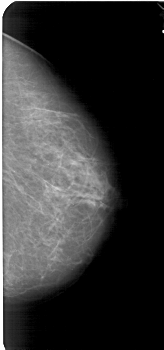

A_1776_1.RIGHT_MLO

RIGHT_MLO LINES 5491 PIXELS_PER_LINE 2671 BITS_PER_PIXEL 12 RESOLUTION 43.5 NON_OVERLAY